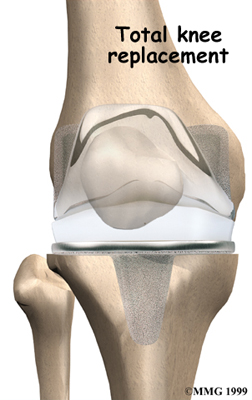

Artificial Knee Replacement

An artificial knee replacement is the ultimate solution for advanced knee OA.

Surgeons prefer not to put a new knee joint in patients younger than 60. This is because younger patients are generally more active and might put too much stress on the joint, causing it to loosen or even crack. A revision surgery to replace a damaged prosthesis is harder to do, has more possible complications, and is usually less successful than a first-time joint replacement surgery.

Related Document: FYZICAL Spanish Fork's Guide to Artificial Joint Replacement of the Knee